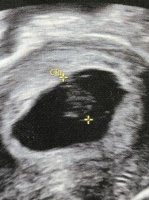

Åja, bare 6-7 ja...det var trist. Men fosteret og morkake flytter jo ikke på seg på de 14 dagene eller? Hmm, ble forvirret jeg nå. Men stemmer det at plasseringen hos meg tilsier gutt?Tror Uke 9 er for sent å bruke ramzi.. skal brukes i uke 6-7 helst

Dette bildet er fra innvendig mellom uke 7 og 8.